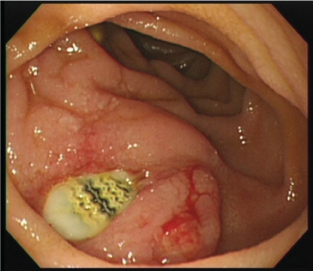

EGD (Figure 1)

Ulceration with a whitish surface was found in the third portion of the duodenum. A purulent exudate was found in the lesion.

Figure 1: Ulceration with white color on the surface was found in the third portion of the duodenum. Purulent exudate was found in the lesion. View Figure 1